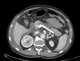

Celiac axis compression syndrome

In medicine, the median arcuate ligament syndrome (MALS, also known as celiac artery compression syndrome, celiac axis syndrome, celiac trunk compression syndrome or Dunbar syndrome) is a rare condition characterized by abdominal pain attributed to compression of the celiac artery and the celiac ganglia by the median arcuate ligament. The abdominal pain may be related to meals, may be accompanied by weight loss, and may be associated with an abdominal bruit heard by a clinician. [Source: Wikipedia ]